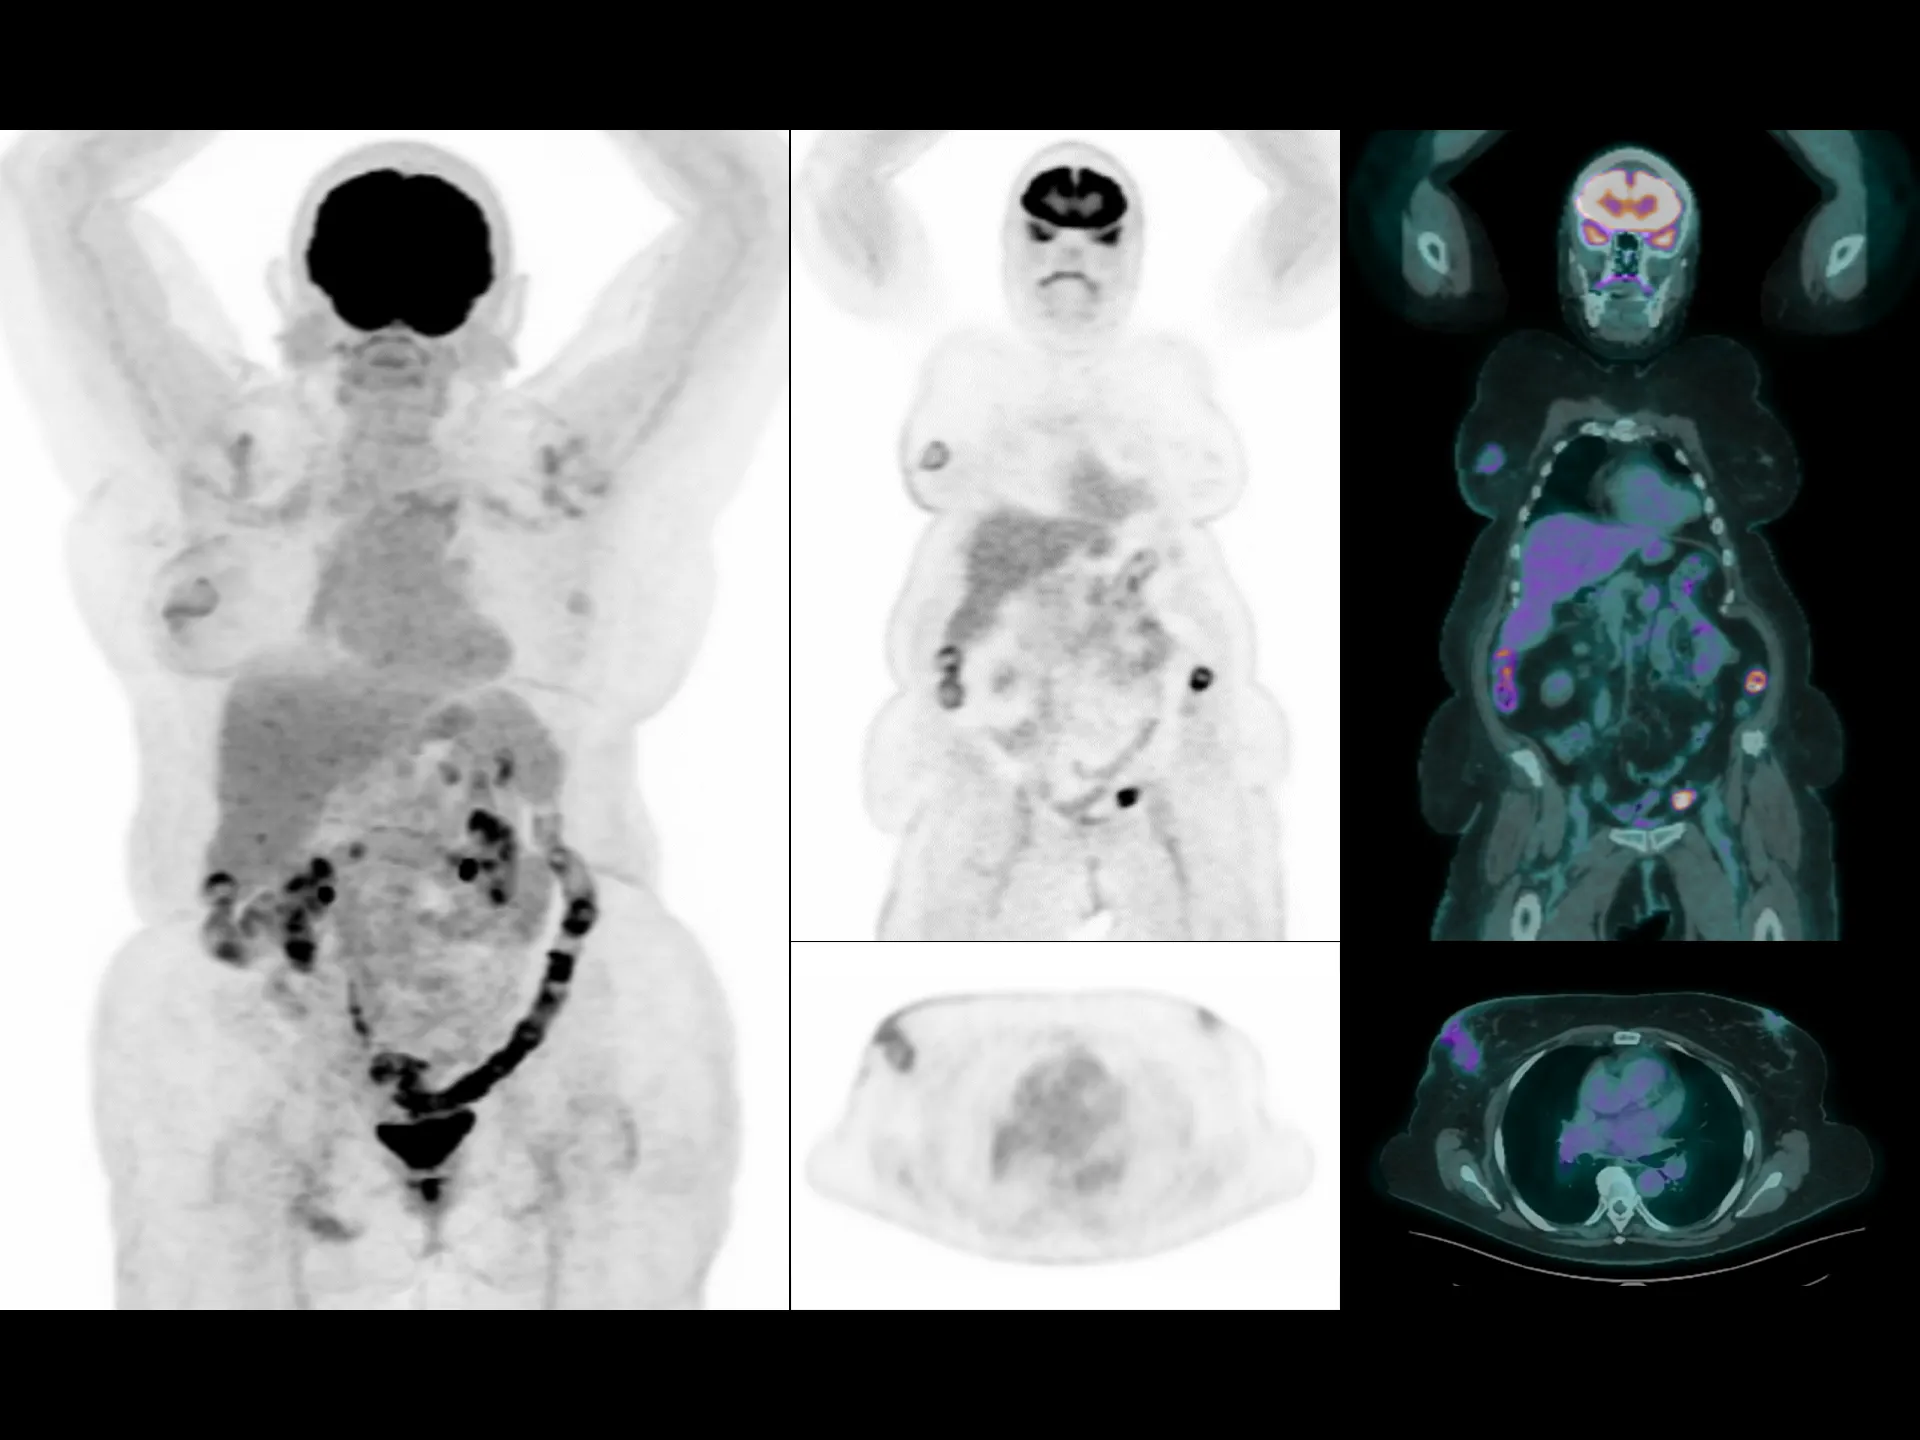

Driven by precision medicine and personalized care, uMI Panvivo offers the top-tier performance based on state-of-the-art detector technology and highly integrated system for better diagnostic confidence and capabilities.

Top-tier Performance

Leading TOF resolution that boosts small lesion detectability and clarity.

High effective sensitivity that benefits from TOF gain leverages better diagnostic accuracy under low dose usage and fast scan time.